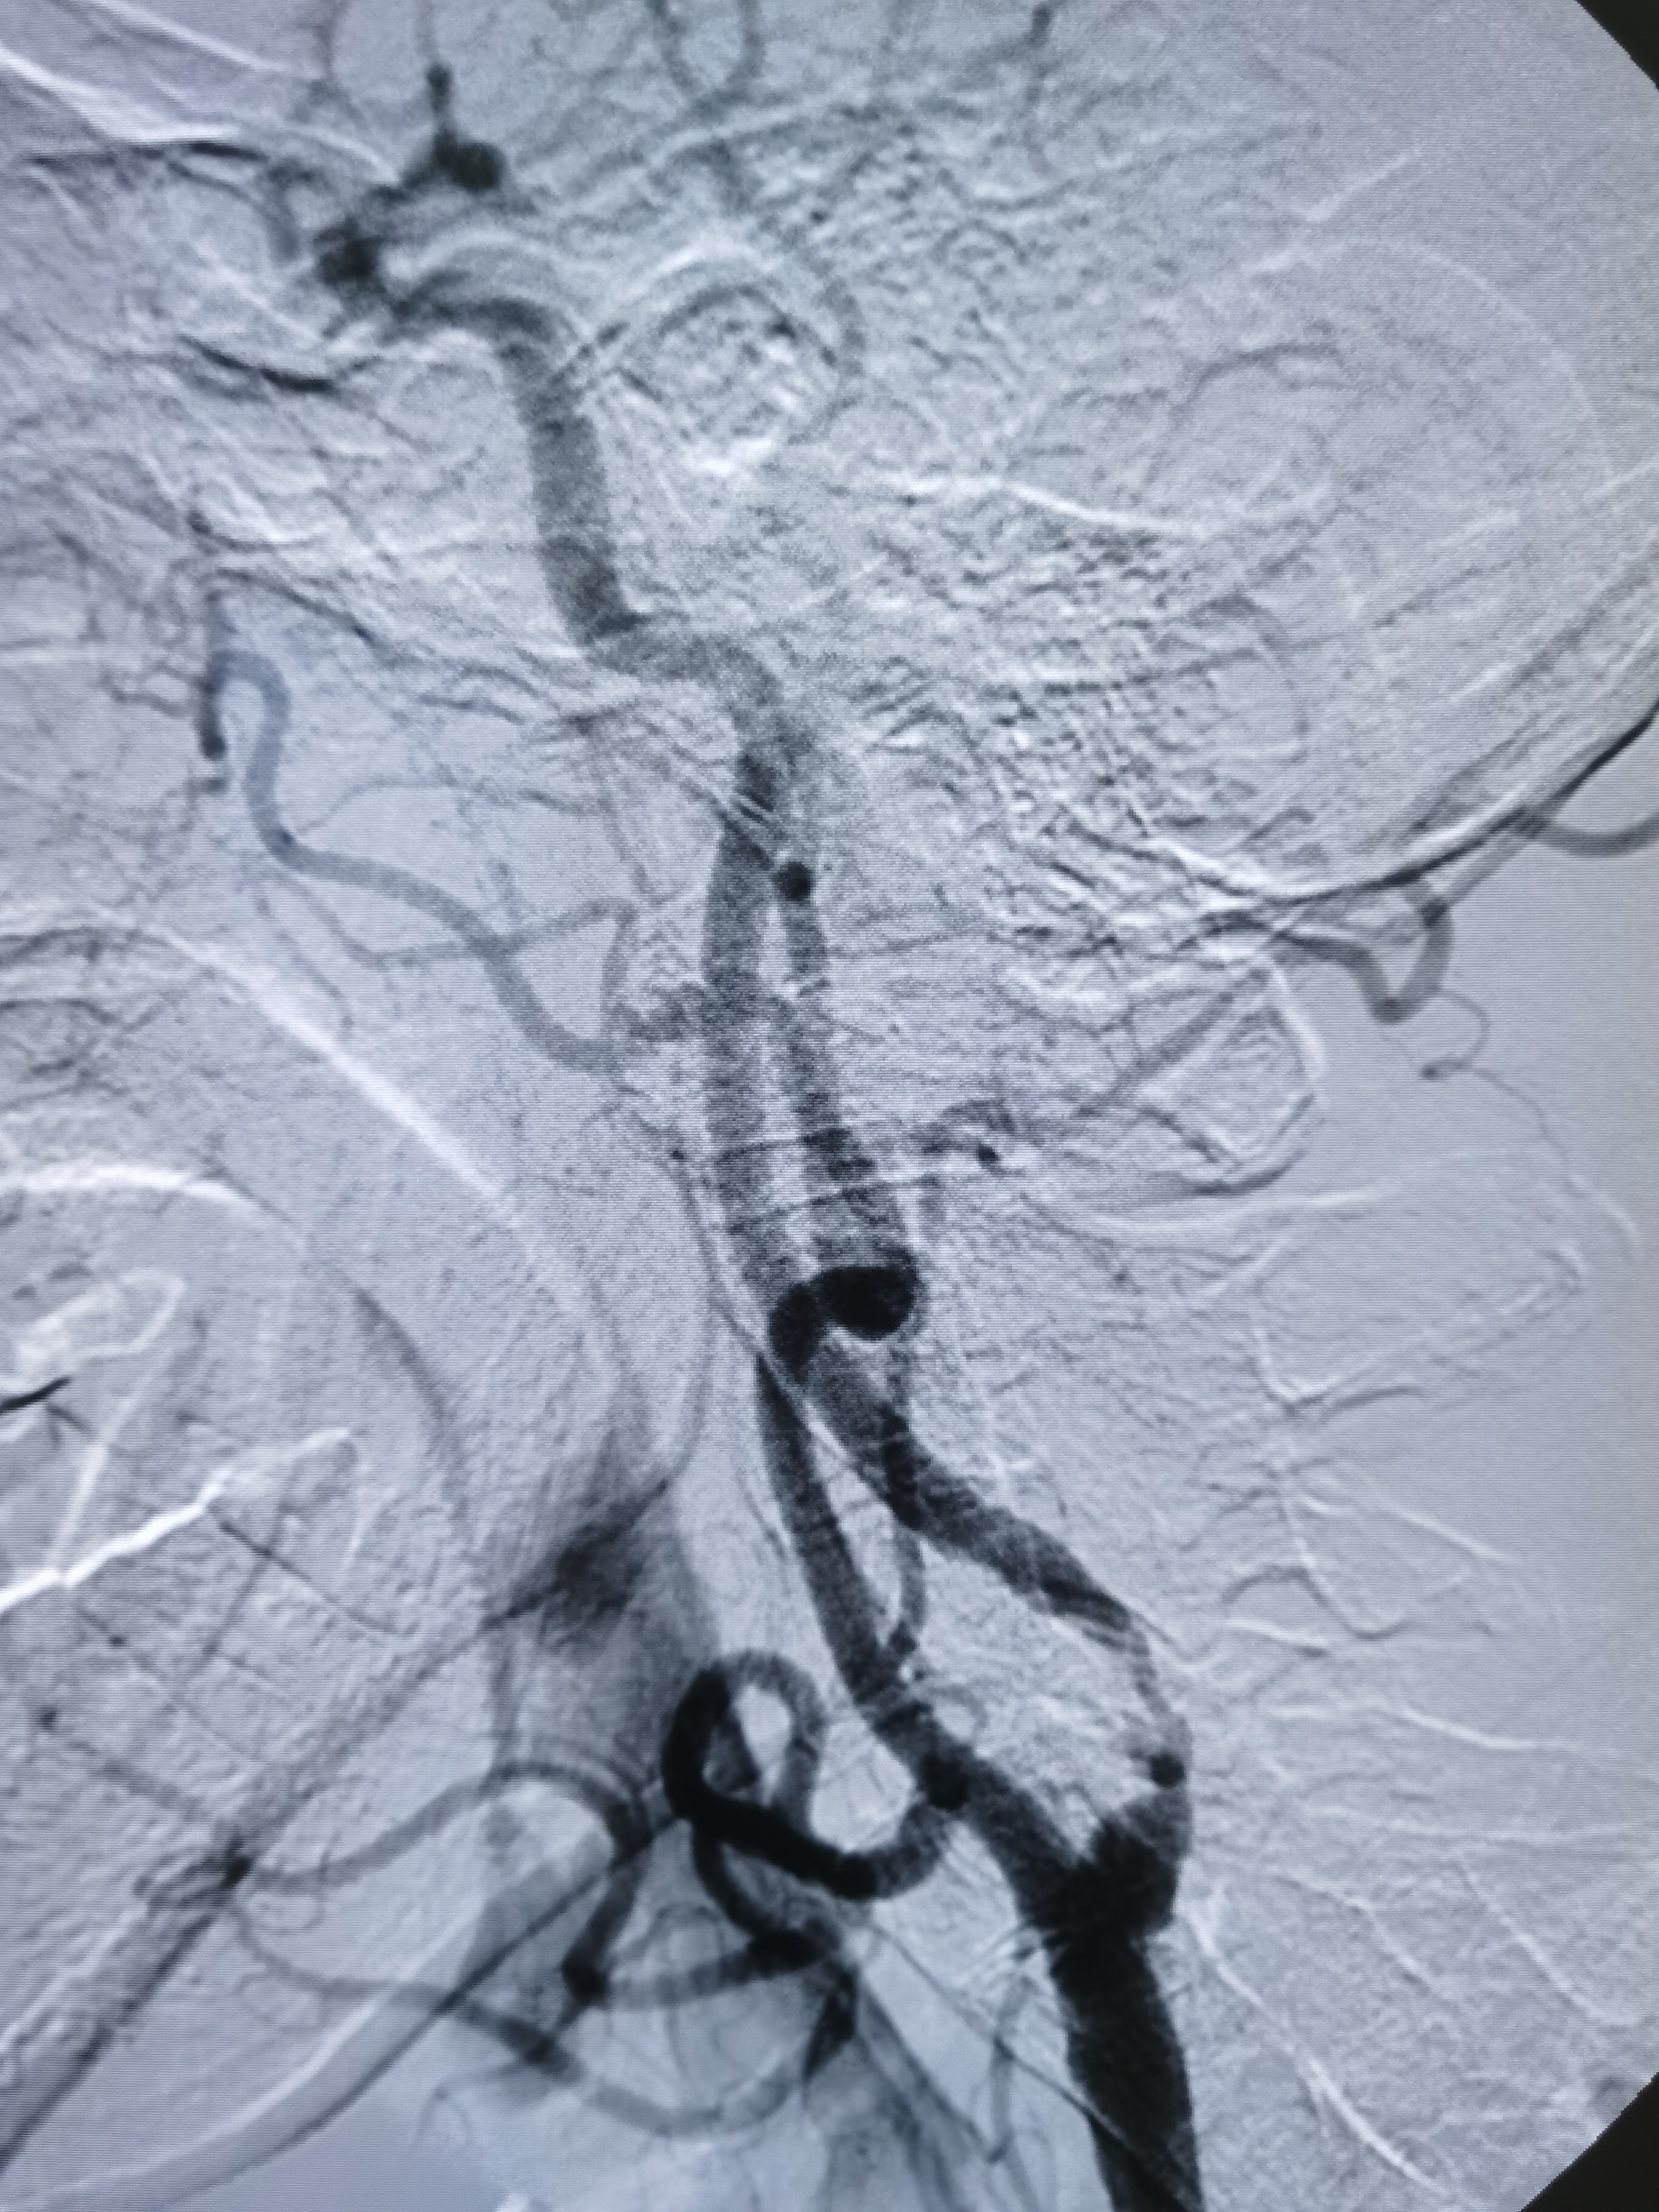

左侧颈内动脉起始部次全闭塞,局部斑块不稳定。

患者造影后明确左侧颈内动脉次全闭塞,斑块不稳定,发生血管急性闭塞风险较大,应积极介入治疗。